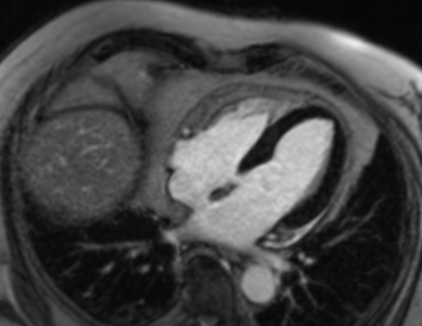

Darstellung des schlagenden Herzens

Darstellung des Herzmuskelgewebes